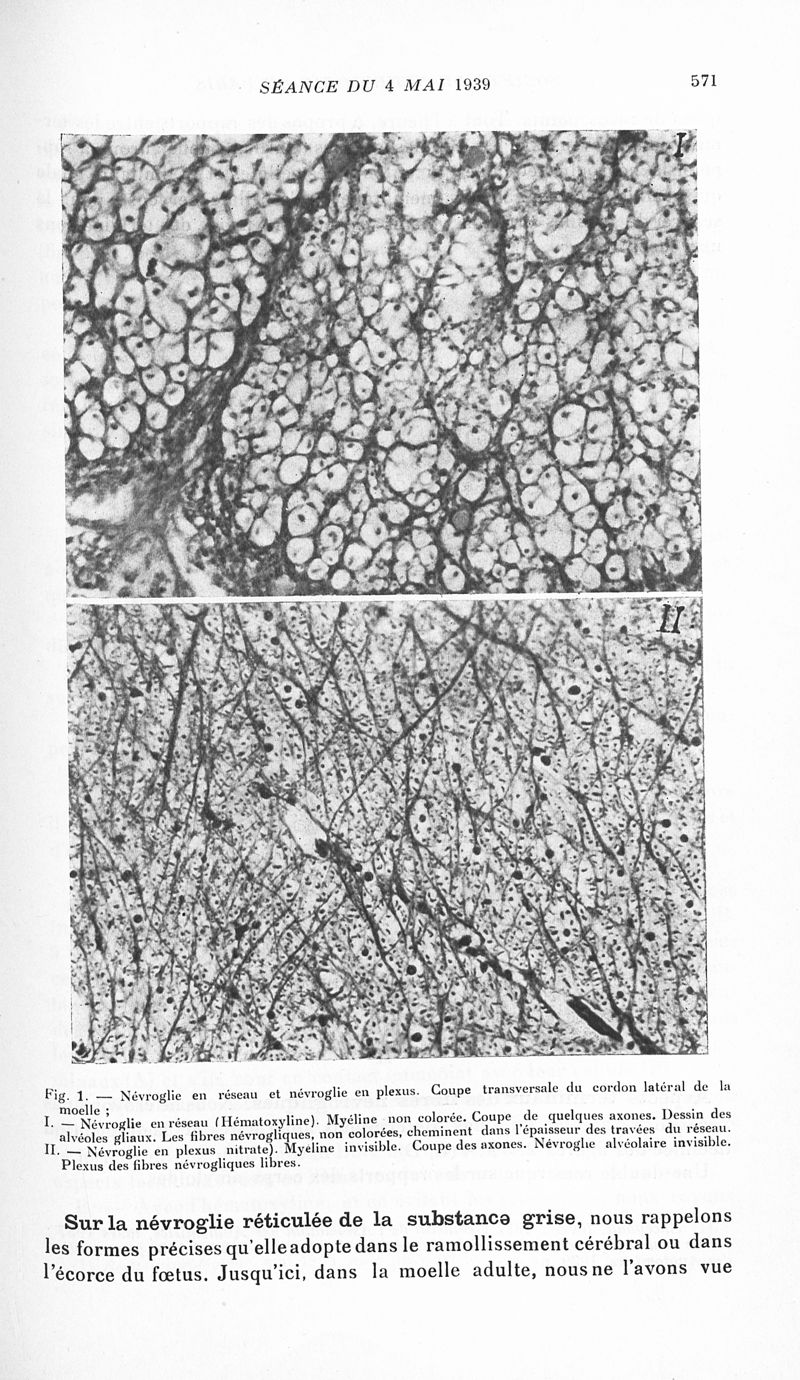

Revue neurologique

1939, vol 1. - Paris : Masson , 1939.